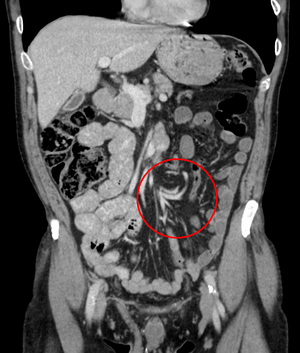

Coronal CT of the abdomen, demonstrating a volvulus as indicated by twisting of the bowel stock

Risk factors include a birth defect known as intestinal malrotation, an enlarged colon, Hirschsprung disease, pregnancy, and abdominal adhesions.[1] Long term constipation and a high fiber diet may also increase the risk.[3] The most commonly affected part of the intestines in adults is the sigmoid colon with the cecum being second most affected.[1] In children the small intestine is more often involved.[4] The stomach can also be affected.[5] Diagnosis is typically with medical imaging such as plain X-rays, a GI series, or CT scan.[1]